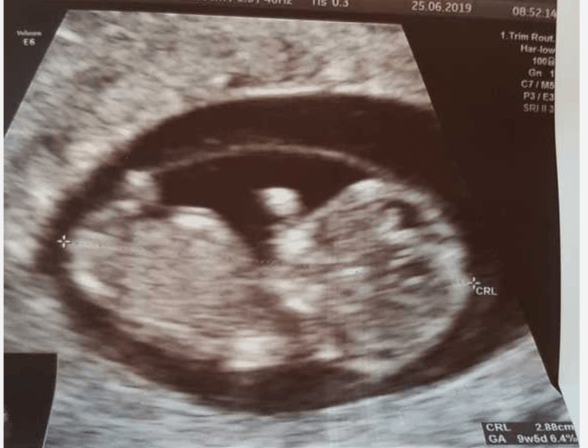

a to mój "bąbelek" z dzisiejszego USG macha na przywitanie ;)

z USG mam 9+5 a z OM 10+1 następna wizyta to już będzie prenatalne dopiero za 3.5 tygodnia